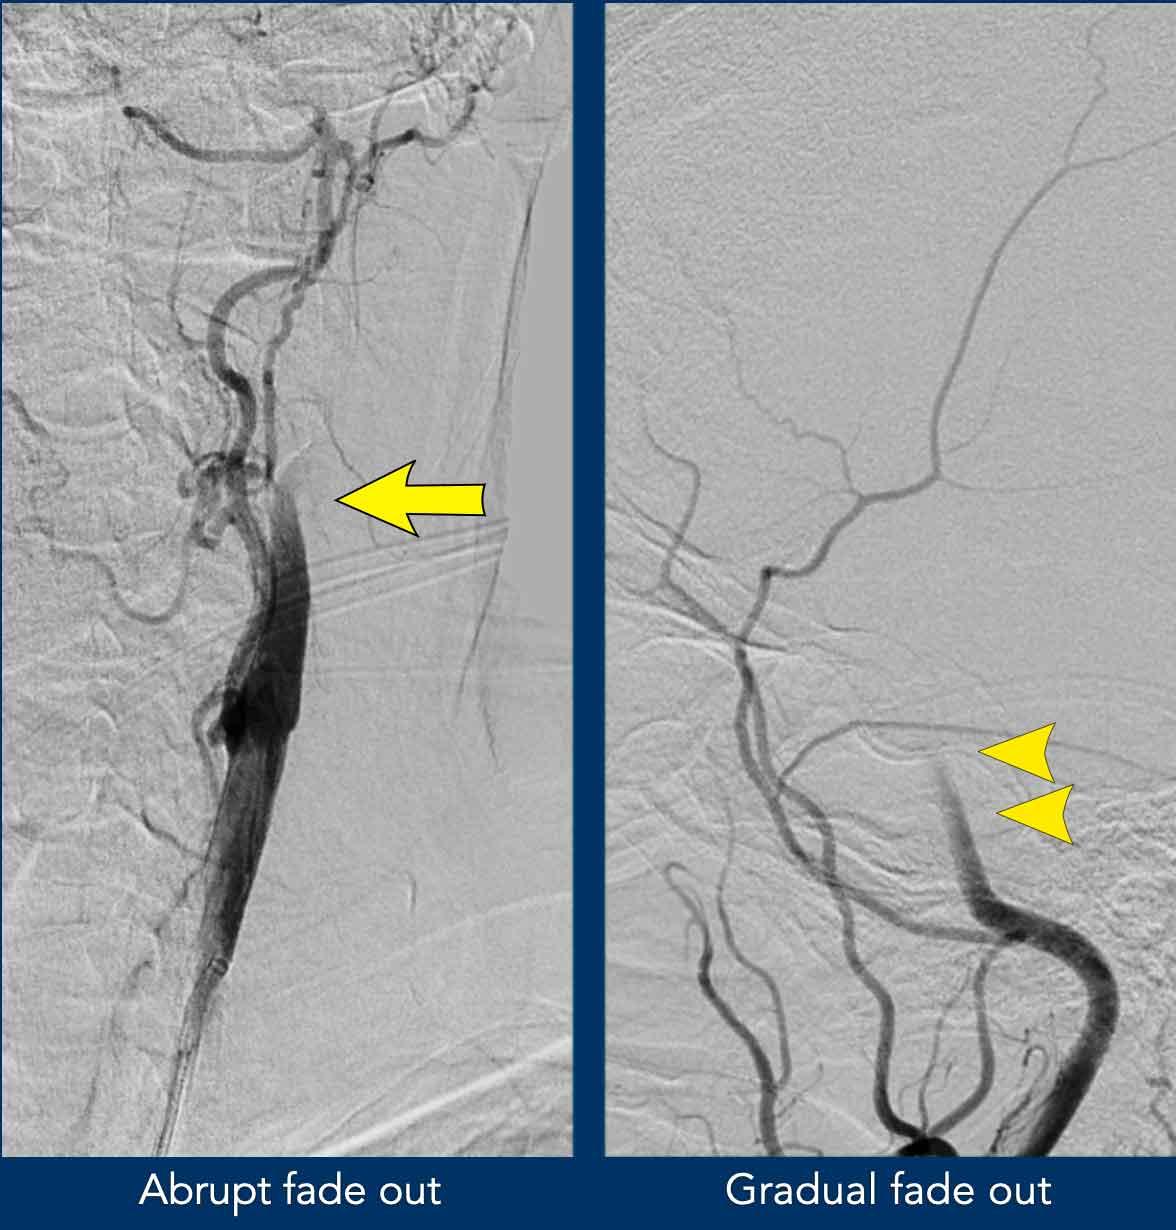

Tắc nghẽn giả trên DSA

DSA cho thấy các hình ảnh tương tự.

Ở bệnh nhân này trong quá trình chụp mạch qua ống thông, ban đầu xuất hiện hình ảnh loang màu nước điển hình của thuốc cản quang trong ICA, mô phỏng hình ảnh tắc nghẽn gần của ICA.

Tuy nhiên, ống thông có thể dễ dàng được đưa vào đoạn ICA xa.

Sau khi bơm thuốc cản quang mạnh hơn, trên tư thế nghiêng thấy hình ảnh tắc nghẽn điển hình tại đỉnh động mạch cảnh (ngay trên mức xuất phát của động mạch mắt).

Không có thuốc cản quang lấp đầy các mạch máu nội sọ.